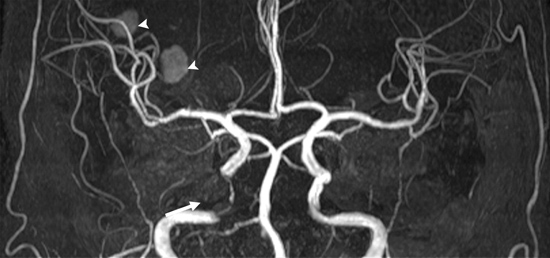

Angiograma por resonancia magnética (RM) de un paciente con estenosis de la arteria carótida interna (flecha). También se muestra un infarto hemorrágico (una acumulación de sangre que parece un moretón) denotado con las flechas. Consulte la página de angiographía por resonancia magnética (ARM) para más información.

Nota: Las imágenes se muestra para fines ilustrativos. No trate de sacar conclusiones comparando esta imagen con otras en el sitio. Solamente los radiólogos calificados deben interpretar las imágenes.